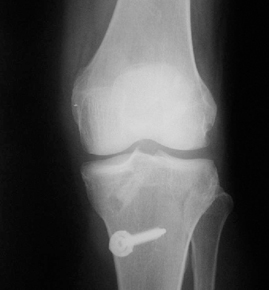

• ACL 손상 방사선 사진4